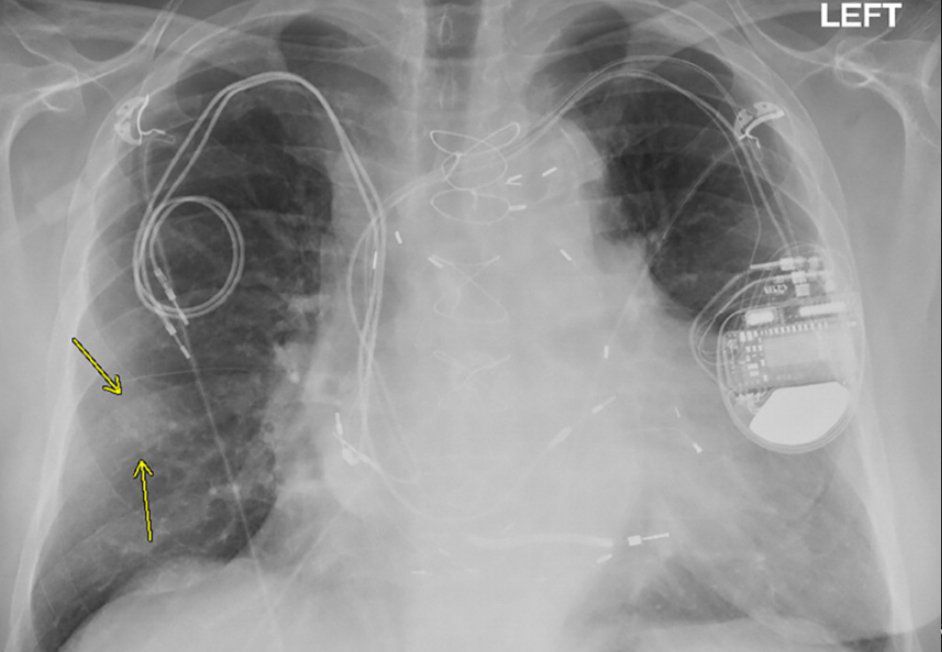

Chest X-ray from a patient included in the study. Posteroanterior view, of a 79-year-old man with history of a previous pacemaker, with abandoned right atrial and right ventricular pacing leads on the right side at time of new cardiac resynchronization therapy defibrillator implant on the left side.